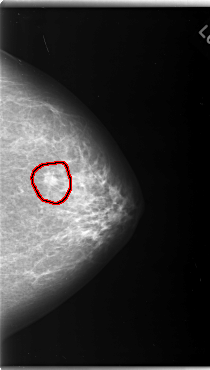

FILE: C_0124_1.LEFT_CC.OVERLAY

TOTAL_ABNORMALITIES 1

ABNORMALITY 1

LESION_TYPE MASS SHAPE OVAL MARGINS SPICULATED

ASSESSMENT 5

SUBTLETY 5

PATHOLOGY MALIGNANT

TOTAL_OUTLINES 1

BOUNDARY